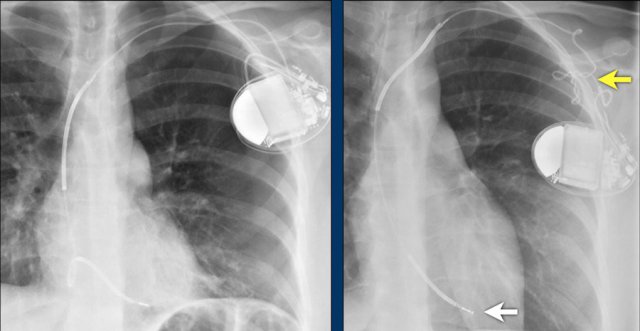

Here a patient with a normally placed ICD on the left image.

Months later there was malfunction due to ICD box and lead rotation (yellow arrow) and retraction (white arrow).

Here another patient with the Twiddler's syndrome.

Notice curling of the lead near the pacemaker and at the tip in the right ventricle (arrows).